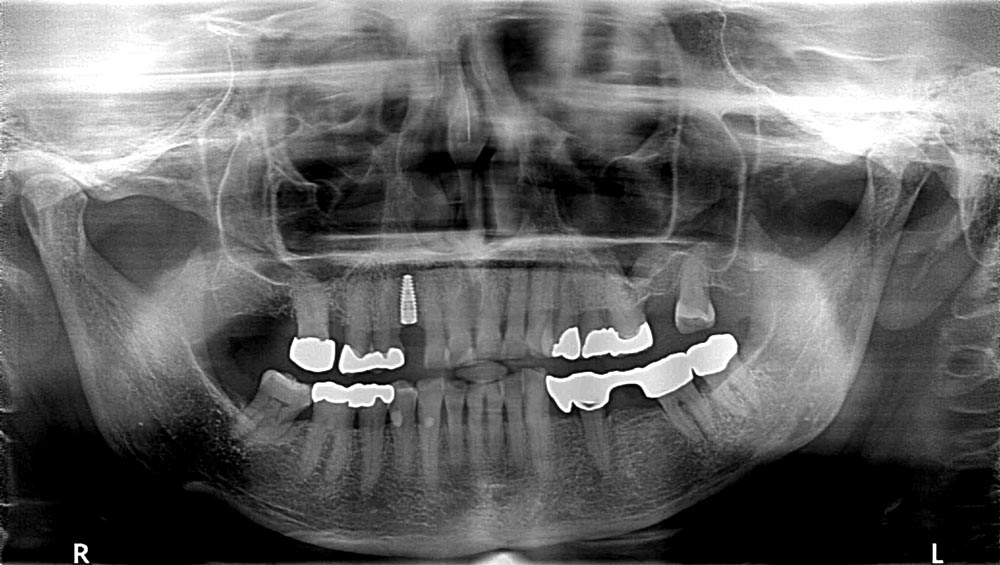

03/12 - Initial CBCT scan

Block augmentation with maxgraft® in the maxilla - PD Dr. Dr. F. Kloss

04/12 - Preoperative radiological situation